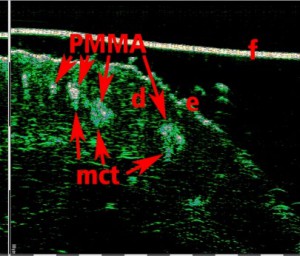

-Έγχυση Πληρωτικών Υλικών (Fillers)